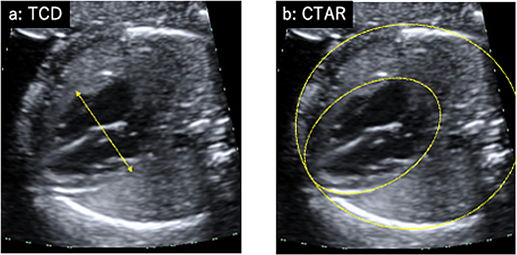

心拡大の評価

一番簡易に行えるのが心拡大の評価である.スクリーニングとして使用できるのがTCD(total cardiac dimension; Fig. 1a)である.三尖弁と僧帽弁の付着部位の心外膜外側を直線的に計測する.妊娠22週以降ではほぼ週数mmと考えることができるため簡易に利用される.経時的な心拡大の評価には心胸郭面積比CTAR(cardio-thoracic area ratio; Fig. 1b)が適している.心臓の面積は心外膜のトレースを,胸郭の面積は皮膚や筋肉を含まない肋骨や脊柱を含む部分をトレース(あるいはellipse法)で計測する.正常値は20~35%である.

Fig. 1 心拡大の評価

CTAR, cardiothoracic area ratio; TCD, total cardiac dimension